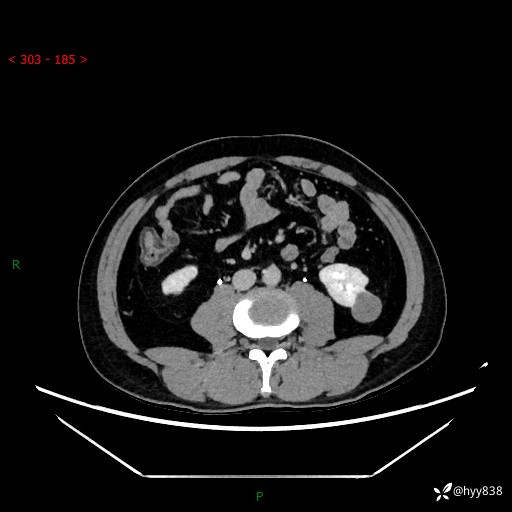

中年男性,左侧腰背部间断性胀痛不适。第一眼“乳头或囊肿”,有无意外---(有结果)

【患者信息】:41岁/男

【主诉】:左侧腰背部间断性胀痛不适1周

【现病史及既往史】:患者1周前无明显诱因出现左侧腰部疼痛,呈间断性胀痛,休息后可缓解,无放射痛,偶可见肉眼血尿,无血块,无尿频尿急尿痛,无夜尿增多,无畏寒发热、咳嗽咳痰等症状。于我院查双肾CT示:左肾占位性病变,左肾下极囊性病变,左肾轻度积水,胆囊多发结石。今为求进一步诊治来我院,门诊以“左肾占位性病变”收治入院。 起病以来,患者精神佳,饮食、睡眠良好,大便正常,小便如上诉,体力体重无明显变化。

【检查】:肾脏CT平扫+增强